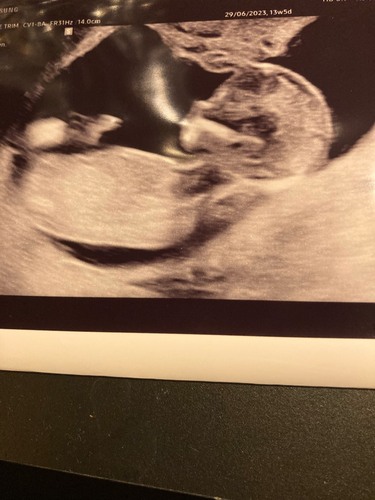

Afgelopen dinsdag de 13 weken echo gehad van ons 🫶🏼je. We hebben 2 hele mooie foto’s mee gekregen en de rest van de foto’s is op een usb stick gezet, eenmaal thuis aangekomen snel de usb stick in de laptop gestopt! Wat bleek de lieve dame had een kort filmpje gemaakt waarbij ons dotje aan het duimen was 🥰 zo verliefd!